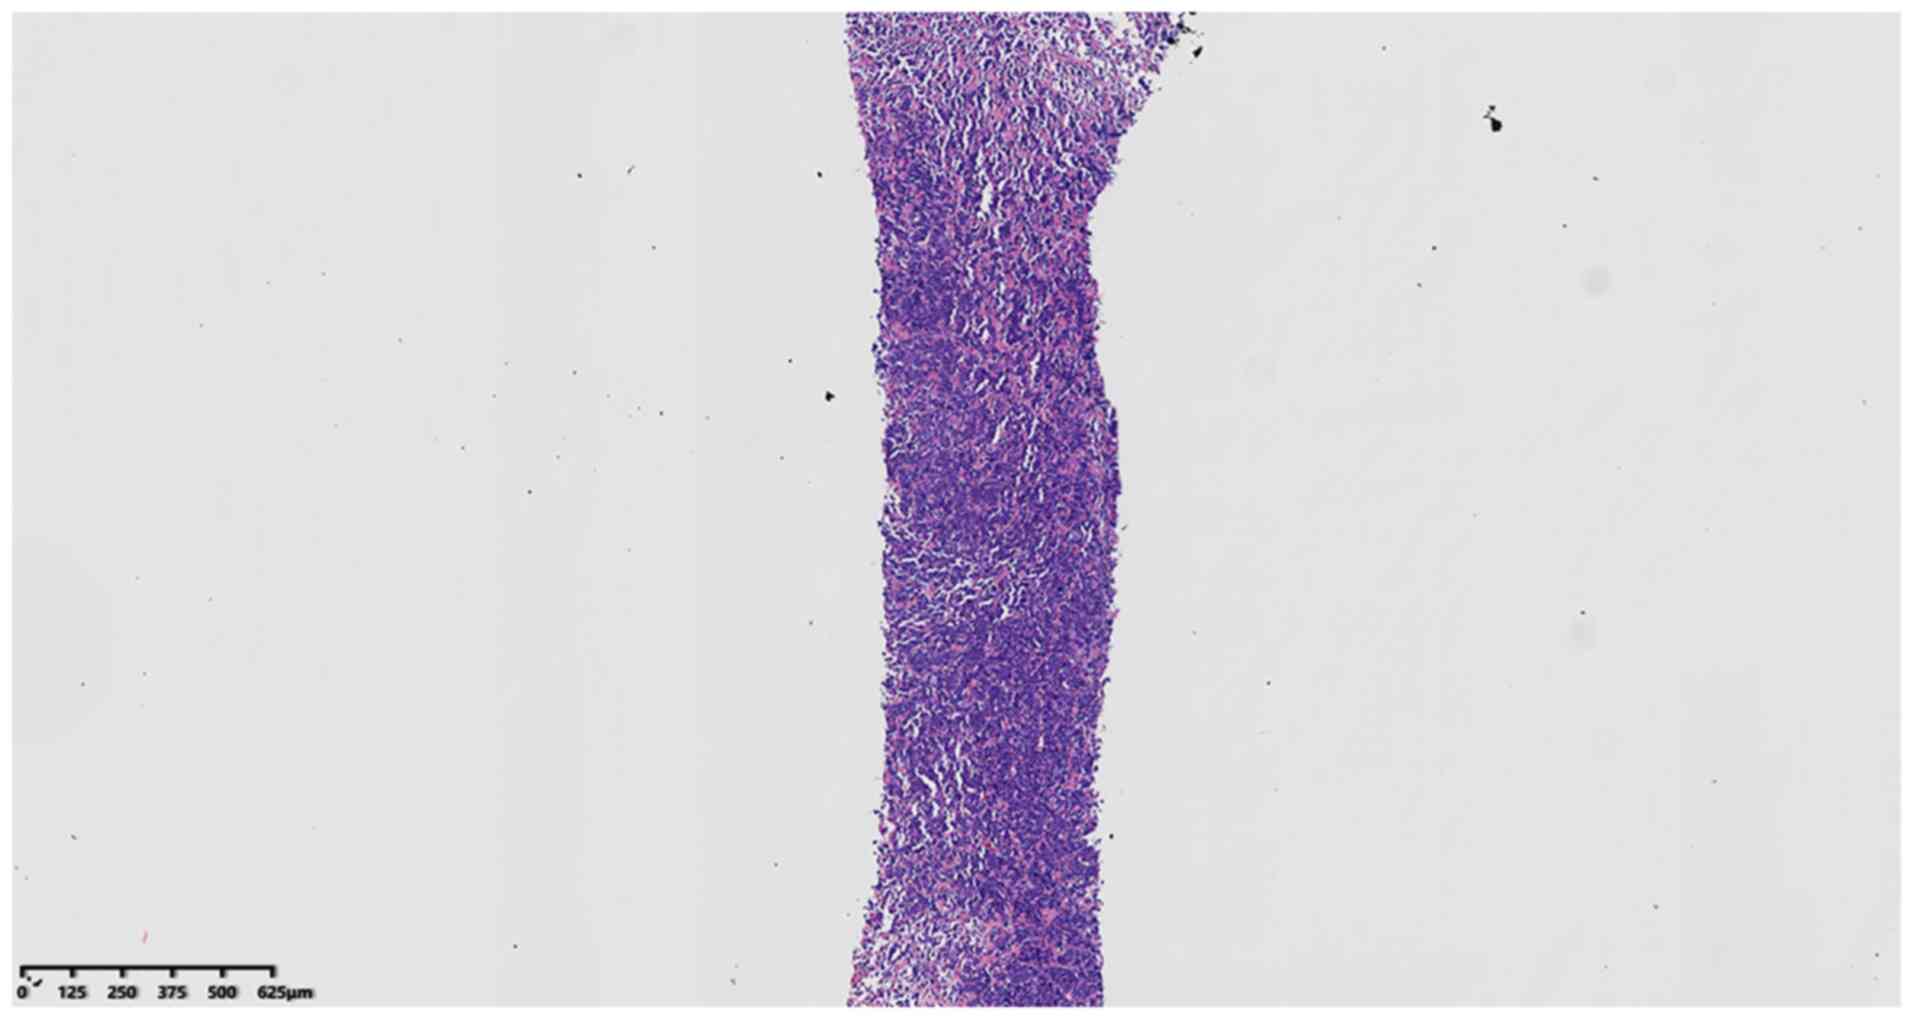

Primary retroperitoneal perirenal CIC rearrangement sarcoma: A case report

Primary retroperitoneal perirenal CIC rearrangement sarcoma is rare. The current case report presents a 69‑year‑old male patient with this pathology, including the clinical features, pathomorphology and immunohistochemistry, and CIC gene rupture detected by fluorescence in situ hybridization (FISH). Furthermore, the relevant literature was reviewed. Histologically, the tumor was composed of diffuse nests of small‑ to medium‑sized juvenile round blue cells with hyperchromatic nuclei, prominent nucleoli and occasional mitotic signs. The tumor involved adipose tissue with no obvious hemorrhagic necrotic foci. Immunohistochemistry indicated scattered expression of CD99 in tumor cells. FISH examination suggested that the CIC gene was fragmented and translocated.